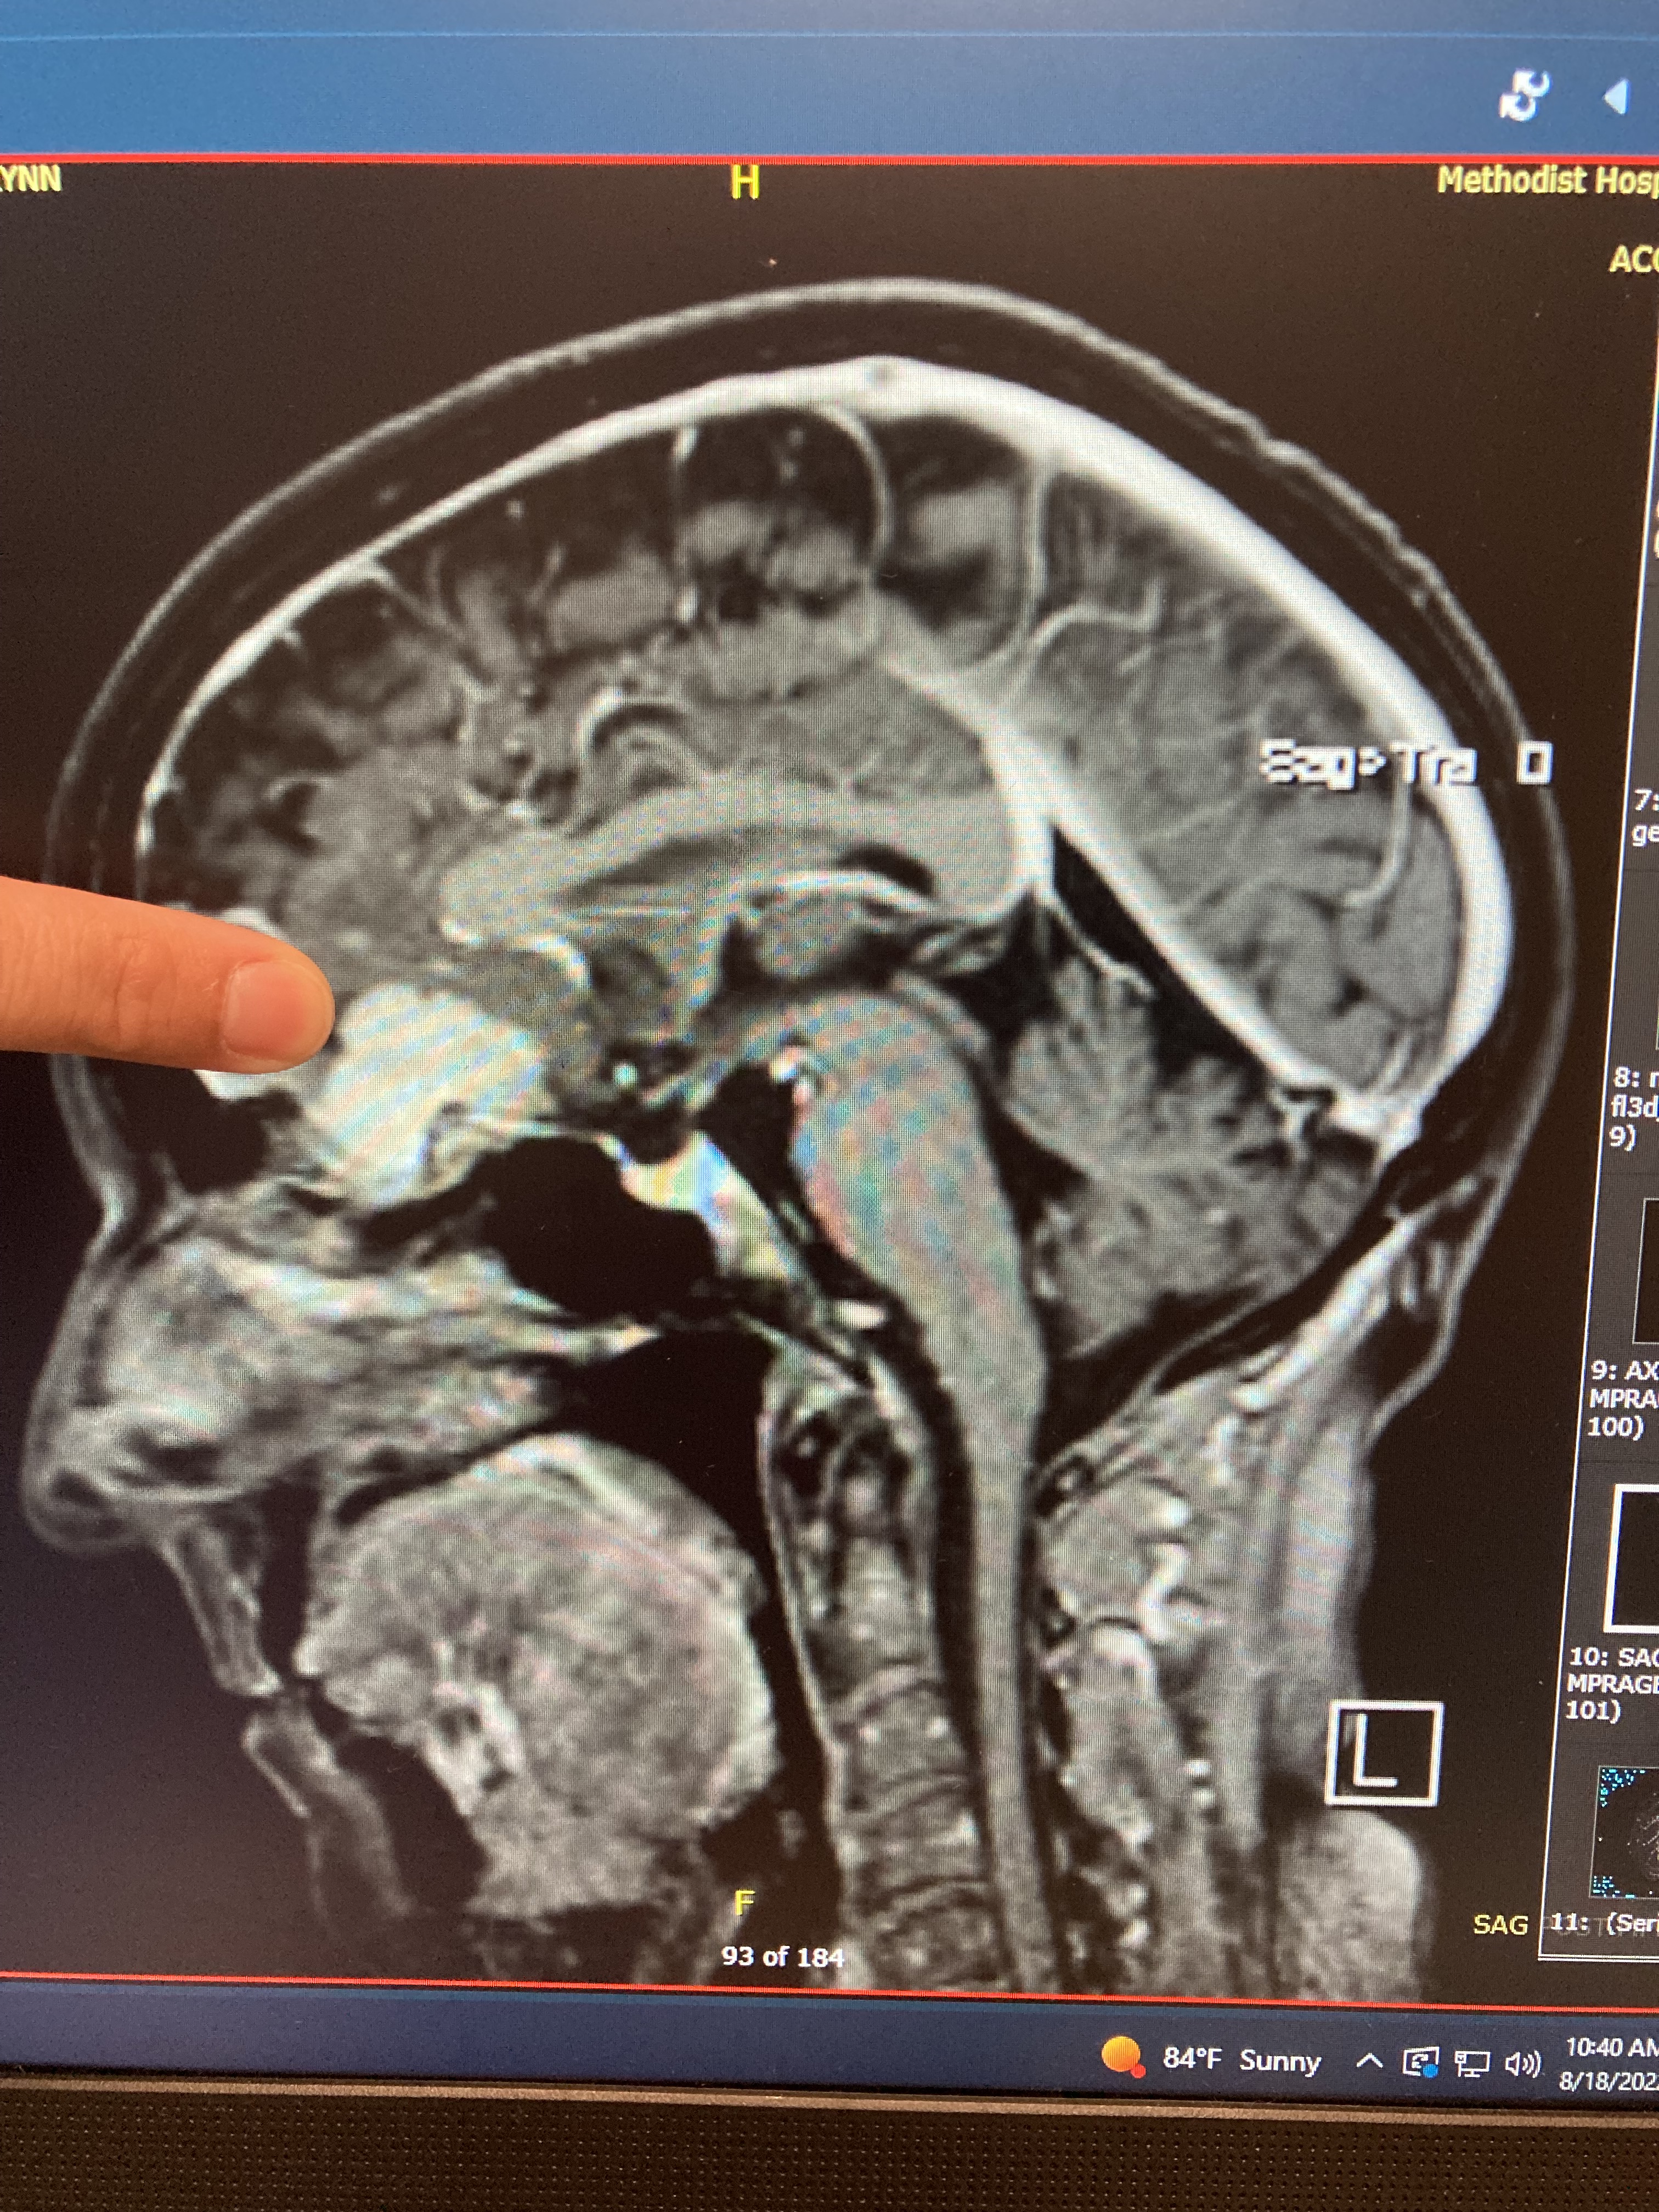

I was seen by two neurosurgeons the week after Vacation Bible school ended. It was then I learned more about the tumor, which was called a meningioma and was located at the base of my skull, under my brain, behind my eyes, and resting on the olfactory nerve. It was about 2.5 cm in diameter. Although most meningiomas are benign and slow-growing, because it was already causing symptoms, it needed to be removed. We scheduled surgery for early August because my retirement was planned for the end of July and there were some things I hoped to accomplish before then.

On the day of surgery I was called to the pre-op area where all the routine things like changing into a hospital gown, admission exam and paperwork, IV start, and visit with the anesthesiologist occurred. But there was a delay before surgery began because the neurosurgeon decided to take another image of the tumor to determine if he could use a different safer approach. A brain MRI with contrast was ordered and done. Although I had to wait an extra three hours to get started, the surgery was hopefully going to be significantly faster and less invasive than originally planned.